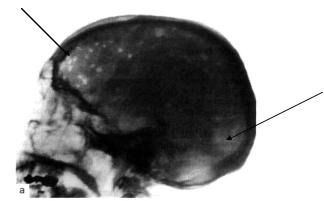

спонтанные переломы. Боль, опухоли, переломы – классическая триада Калера – типична для больных ММ в поздних стадиях и при агрессивных формах болезни. У 10% больных развивается синдром сдавления спинного мозга с нижним парапарезом и параплегией. Рентгенологически – генерализованный остеопороз, единичные или множественные очаги остеолиза, патологические переломы, иногда миелому сопровождает развитие очагового или диффузного остеосклероза.Наиболее характерны поражения в костях черепа: отдельные дефекты выглядят как бы изъеденными молью или выбитыми пробойником(рис. 7-1).

Рис. 7-1. Поражение черепа у больного ММ